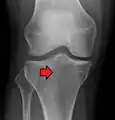

Lipohermatrosis (presencia de grasa y sangre provenientes de la médula ósea en el espacio de la articulación después de una fractura interarticular) visto con Rayos-X en una persona con una leve fractura de meseta tibial.

Lipohermatrosis debida a una fractura de meseta tibial